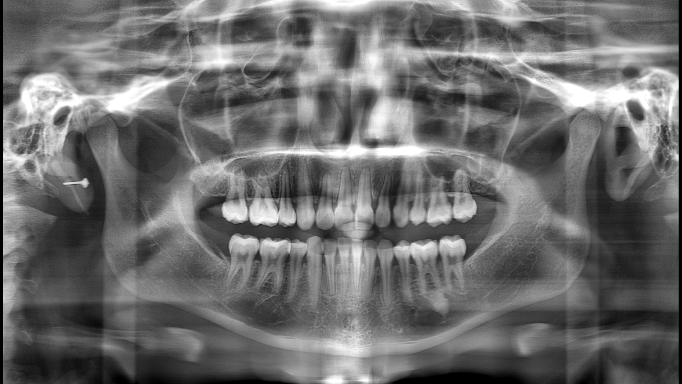

▲“ "The Effect of 'PD' Technology in Panoramic Images"

▲From left to right: Original Image, Mainstream Algorithm, "PD" Technology

▲Advantages of "PD" Technology: Deep Restoration of Image Details